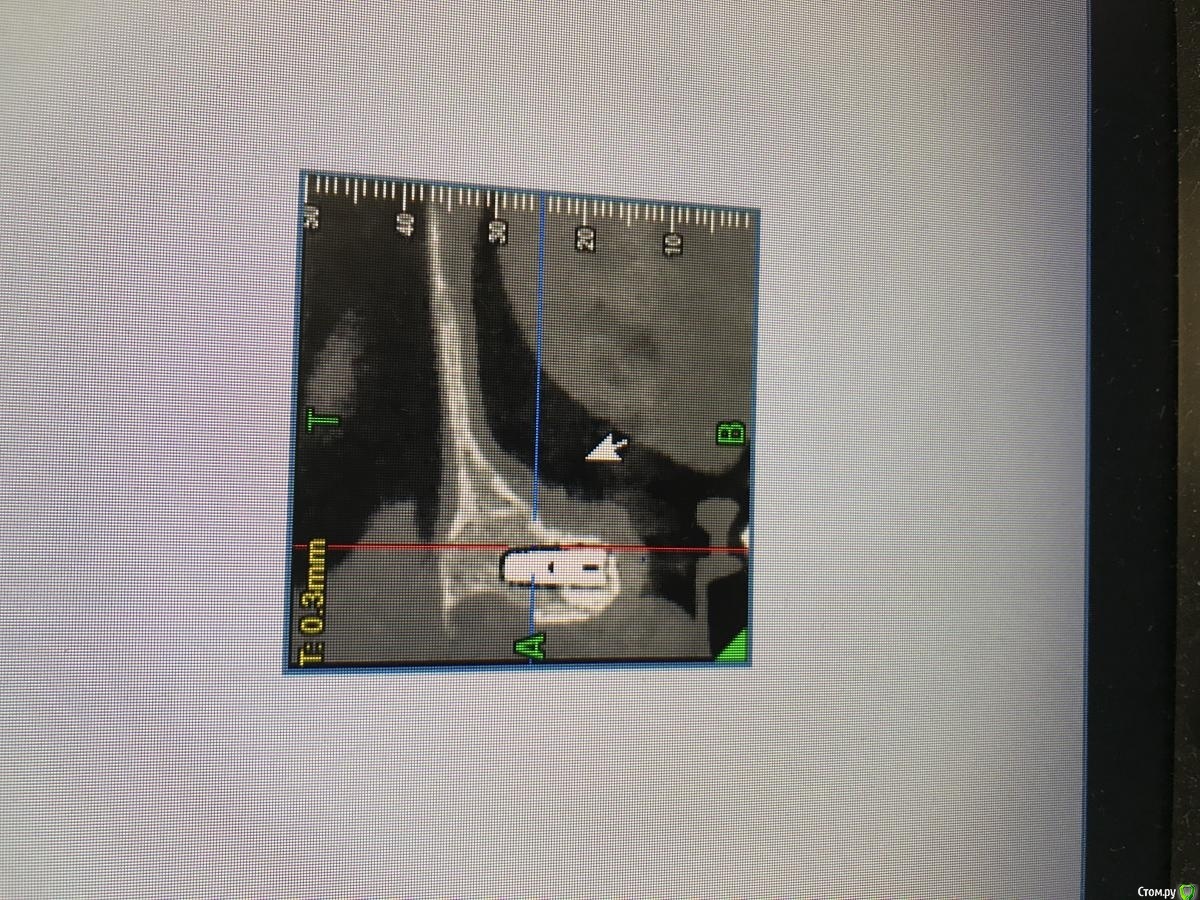

MakovskyAlexandr Опубликовано 8 октября, 2020 Поделиться Опубликовано 8 октября, 2020 Здравствуйте, люди добрые, подскажите пожалуйста.Удалены 2 Корня(21 и 12). Пациентка отказалась от трёх коронок, изъявила желание именно двумя восстановить.Удалены корни - установлены импланты анкилоз А3.5 11 и 14 мм.Выполнена костная пластика , материал ограждён мембраной- все по классике, мембрана фиксирована пинами. Я так понимаю произошло смещение материала( то от гематома, то ли отёк такой). Как быть дальше? Ждать интеграции и подсаживать потом аутотрансплантат?Спасибо огромное. Ссылка на комментарий

MakovskyAlexandr Опубликовано 19 апреля, 2021 Автор Поделиться Опубликовано 19 апреля, 2021 Ссылка на комментарий

Дмитрий Л. Опубликовано 19 апреля, 2021 Поделиться Опубликовано 19 апреля, 2021 Интересно как решите вопрос протетики. Я бы с техником посоветовался и хотя бы ваксап попросил на 3 ед. Обдумал бы вариант препарирования соседей и покрытия их коронками меньшими по размеру. Если заморочиться. А так вроде норм. Ссылка на комментарий